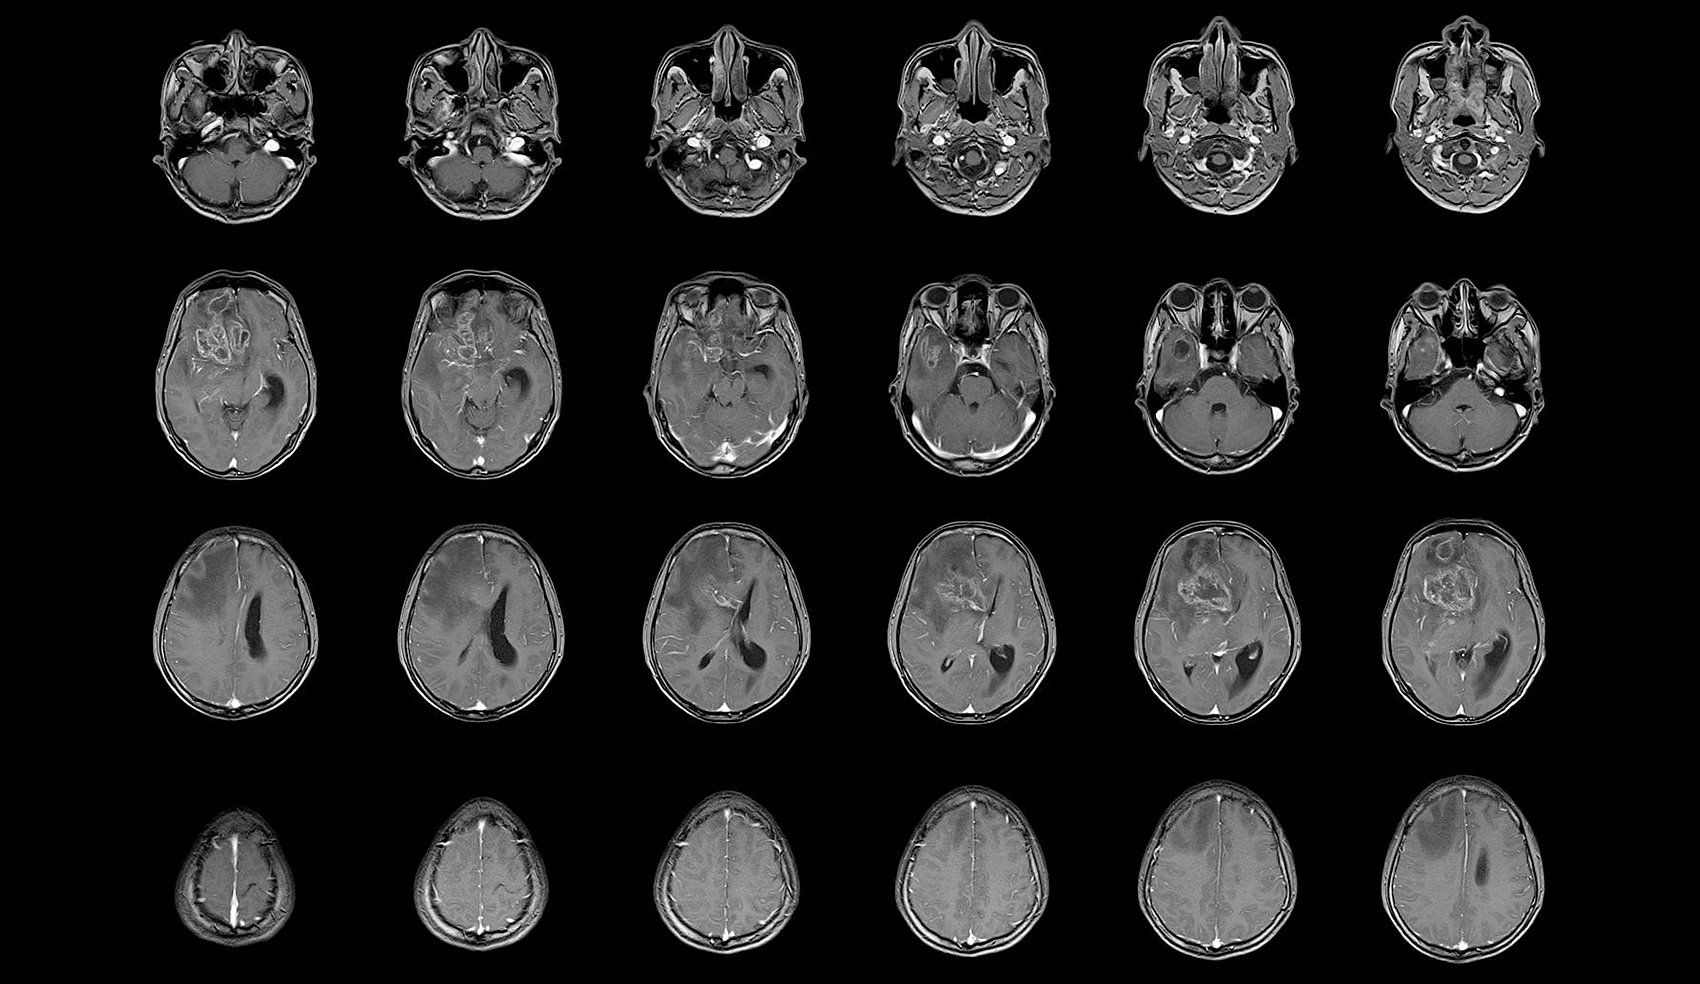

胶质瘤放射治疗是一种常见的治疗方法

胶质瘤放射治疗技术,昆明治疗晚期胶质瘤医院推荐-昆明医科肿瘤医院胶质瘤是一种严重的脑部恶性肿瘤,它起源于神经胶质细胞,通常发生在大脑的深处。胶质瘤的治疗通常涉及手术、放疗和化疗。在这篇文章中,我们将重点介绍胶质瘤放射治疗的相关知识。放射治疗是一种常见的治疗胶质...

胶质瘤放射治疗的适应症有哪些

胶质瘤的早期症状,昆明治疗胶质瘤医院哪家好-昆明医科肿瘤医院胶质瘤是一种常见的脑部肿瘤,通常需要采用综合治疗来控制其生长和扩散。放射治疗作为胶质瘤治疗中的重要手段,可以减少肿瘤的大小和数量,从而改善患者的生活质量和延长生存期。本文将介绍胶质瘤放射治疗的基本情况...

胶质瘤放射治疗的基本原理、治疗方法和注意事项

胶质瘤放射治疗效果,昆明晚期胶质瘤治疗医院推荐-昆明医科肿瘤医院胶质瘤是一种常见的恶性脑肿瘤,常常难以完全切除。放射治疗是治疗胶质瘤的重要手段之一,可以通过辐射杀死肿瘤细胞、抑制肿瘤生长和复发,提高患者的生存率和生存质量。本文将介绍胶质瘤放射治疗的基本原理、治...

胶质瘤放疗相关知识科普

晚期胶质瘤治疗方案,昆明胶质瘤医院效果好的医院-昆明医科肿瘤医院胶质瘤是一种恶性肿瘤,起源于脑中的胶质细胞,是脑肿瘤中最常见的类型。胶质瘤通常会通过手术切除、放疗和化疗等治疗方法进行治疗。其中,放疗治疗在胶质瘤治疗中扮演着重要的角色,本篇文章将会详细介绍胶质瘤...

胶质瘤的治疗效果到底好不好

胶质瘤治疗效果如何,昆明胶质瘤医院哪家还不错-昆明医科肿瘤医院放射治疗是胶质瘤治疗的常用方法之一。下面我们来了解一下放射治疗在胶质瘤治疗中的作用。放射治疗是利用高能射线或粒子对癌细胞进行杀伤的一种治疗方法。放射治疗可以直接杀死癌细胞或阻止它们继续生长和扩散。对...

胶质瘤的治疗方式有哪些

胶质瘤的治疗方式,昆明胶质瘤医院排名推荐-昆明医科肿瘤医院胶质瘤是一种难以治愈的恶性肿瘤,因其高度侵袭性和复发性而难以治疗。目前,治疗胶质瘤的方法主要包括手术切除、放射治疗和化学治疗等综合治疗手段。本文将介绍各种治疗方法的优缺点以及选择治疗方案的考虑因素。手术...

胶质瘤的预后取决于多种因素

胶质瘤的预后效果,昆明胶质瘤医院哪家好-昆明医科肿瘤医院脑胶质瘤是由于大脑和脊髓胶质细胞癌变所产生的、最常见的原发性颅脑肿瘤。年发病率约为3-8人/10万人口。如同其他肿瘤(疾病)一样,胶质瘤也是由于先天的遗传高危因素和环境的致癌因素相互作用所导致的。一些已知...